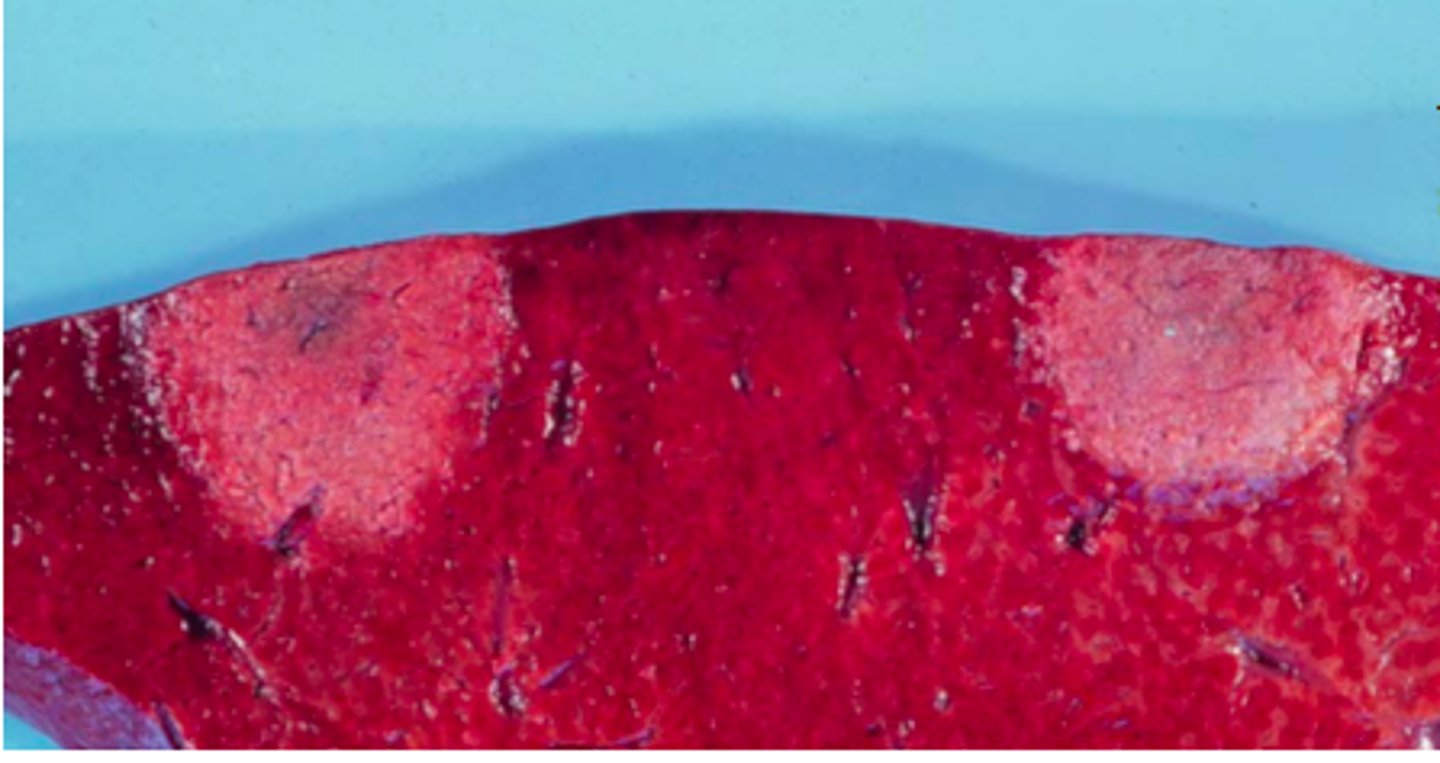

Kronisk multifokal, fibrøs, interstitiel hepatitis

Ætiologi: migration af Ascaris suum larver

Lever fra svin, hvad er den patoanatomiske diagnose og ætiologien?

Kronisk multifokal, fibrøs, interstitiel hepatitis

Ætiologi: migration af Ascaris suum larver

Lever fra svin, hvad er den patoanatomiske diagnose og ætiologien?